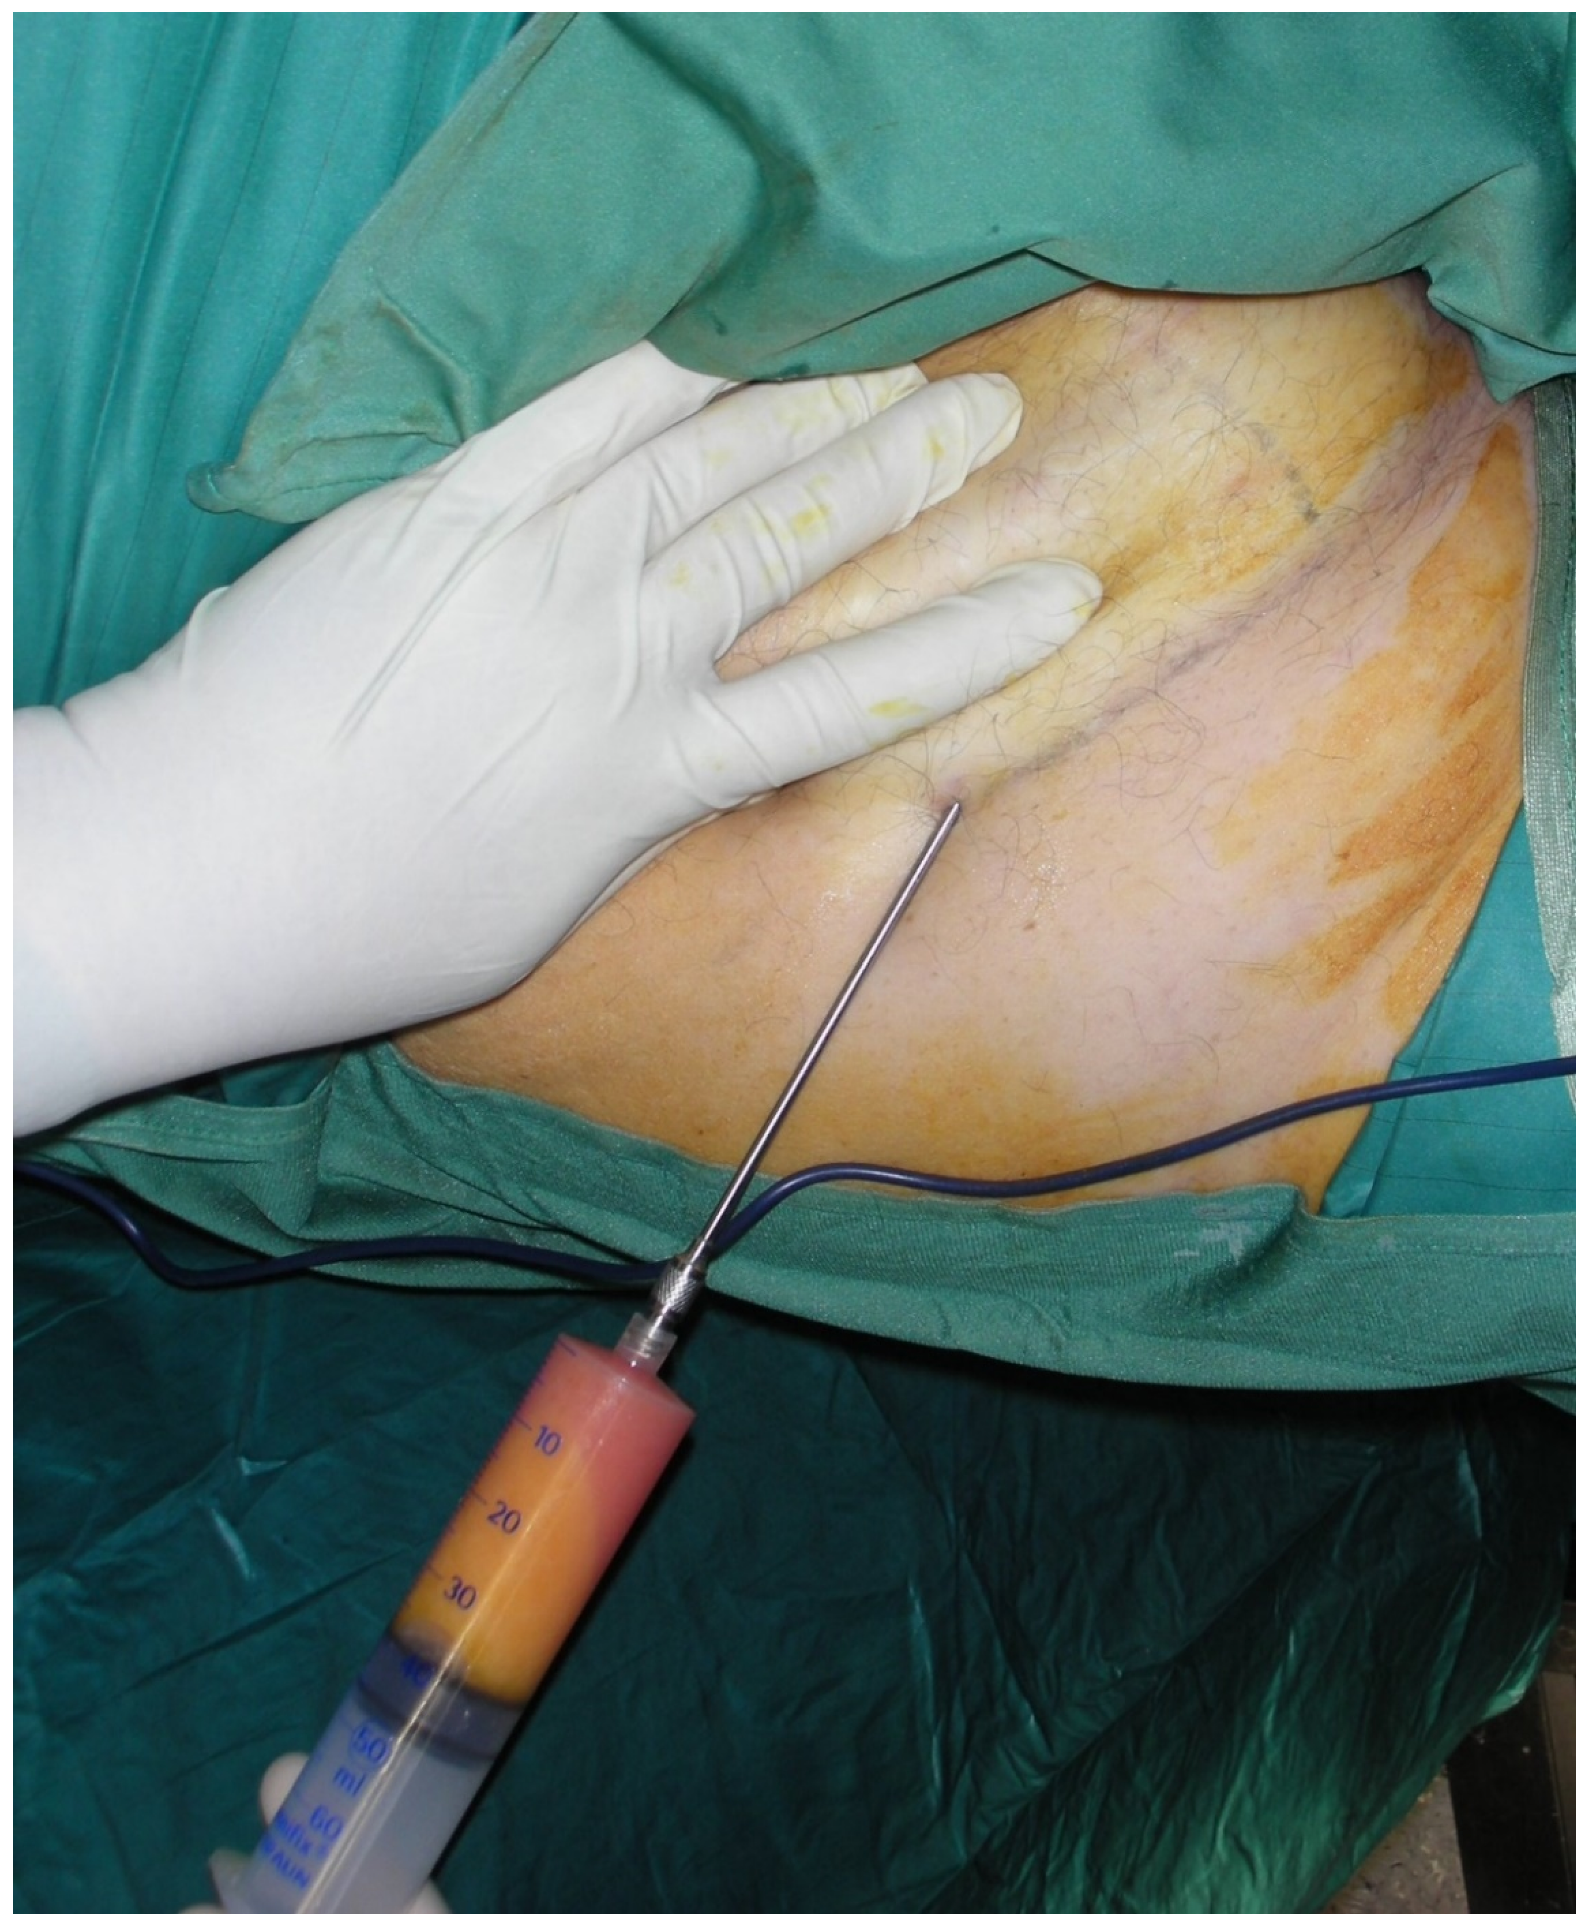

2. Materials and Methods

- Group A (n = 9)—patients who received sequestrectomy and autologous fat graft;

- Group B (n = 12)—patients who received sequestrectomy alone.

Treatment Protocol